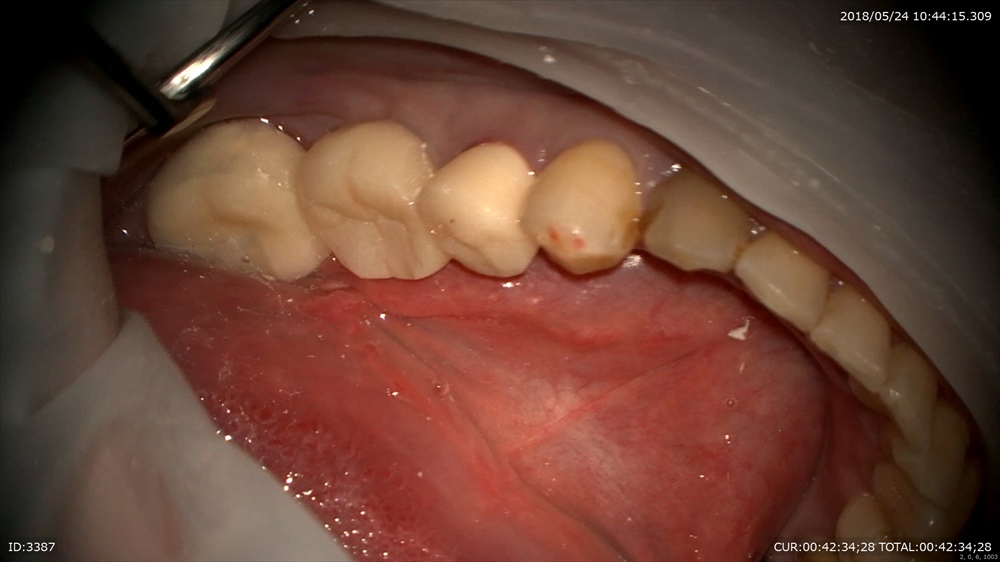

この状態から

仮歯セットポンティック部を押しています。

次回最終形成をしていきます。

この様に全ての治療にマイクロスコープを使用することで治療期間の短縮や無痛が可能になります。